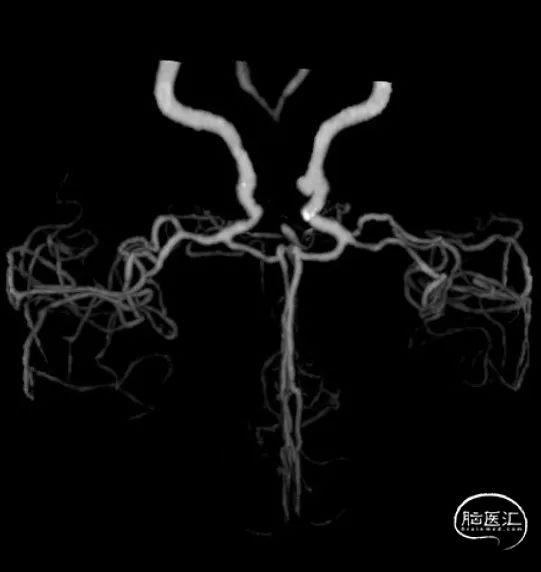

➢2023年11月13日

头颈部CTA:头颈部动脉粥样硬化,右侧椎动脉颅内段及两侧大脑后动脉重度狭窄,基底动脉闭塞。

➢2023年11月14日

头颅MRI平扫+HRMRI:脑桥、中脑急性/亚急性脑梗死;双侧桥臂变性。

HRMRI:基底动脉闭塞并斑块合并局部出血;左侧大脑后动脉P1段斑块形成,相应管腔闭塞,左侧椎动脉V2-V4段斑块形成,相应管腔中重度狭窄,左侧椎动脉V4段管壁弥漫性增厚,相应管腔中度狭窄;右侧大脑后动脉纤细。